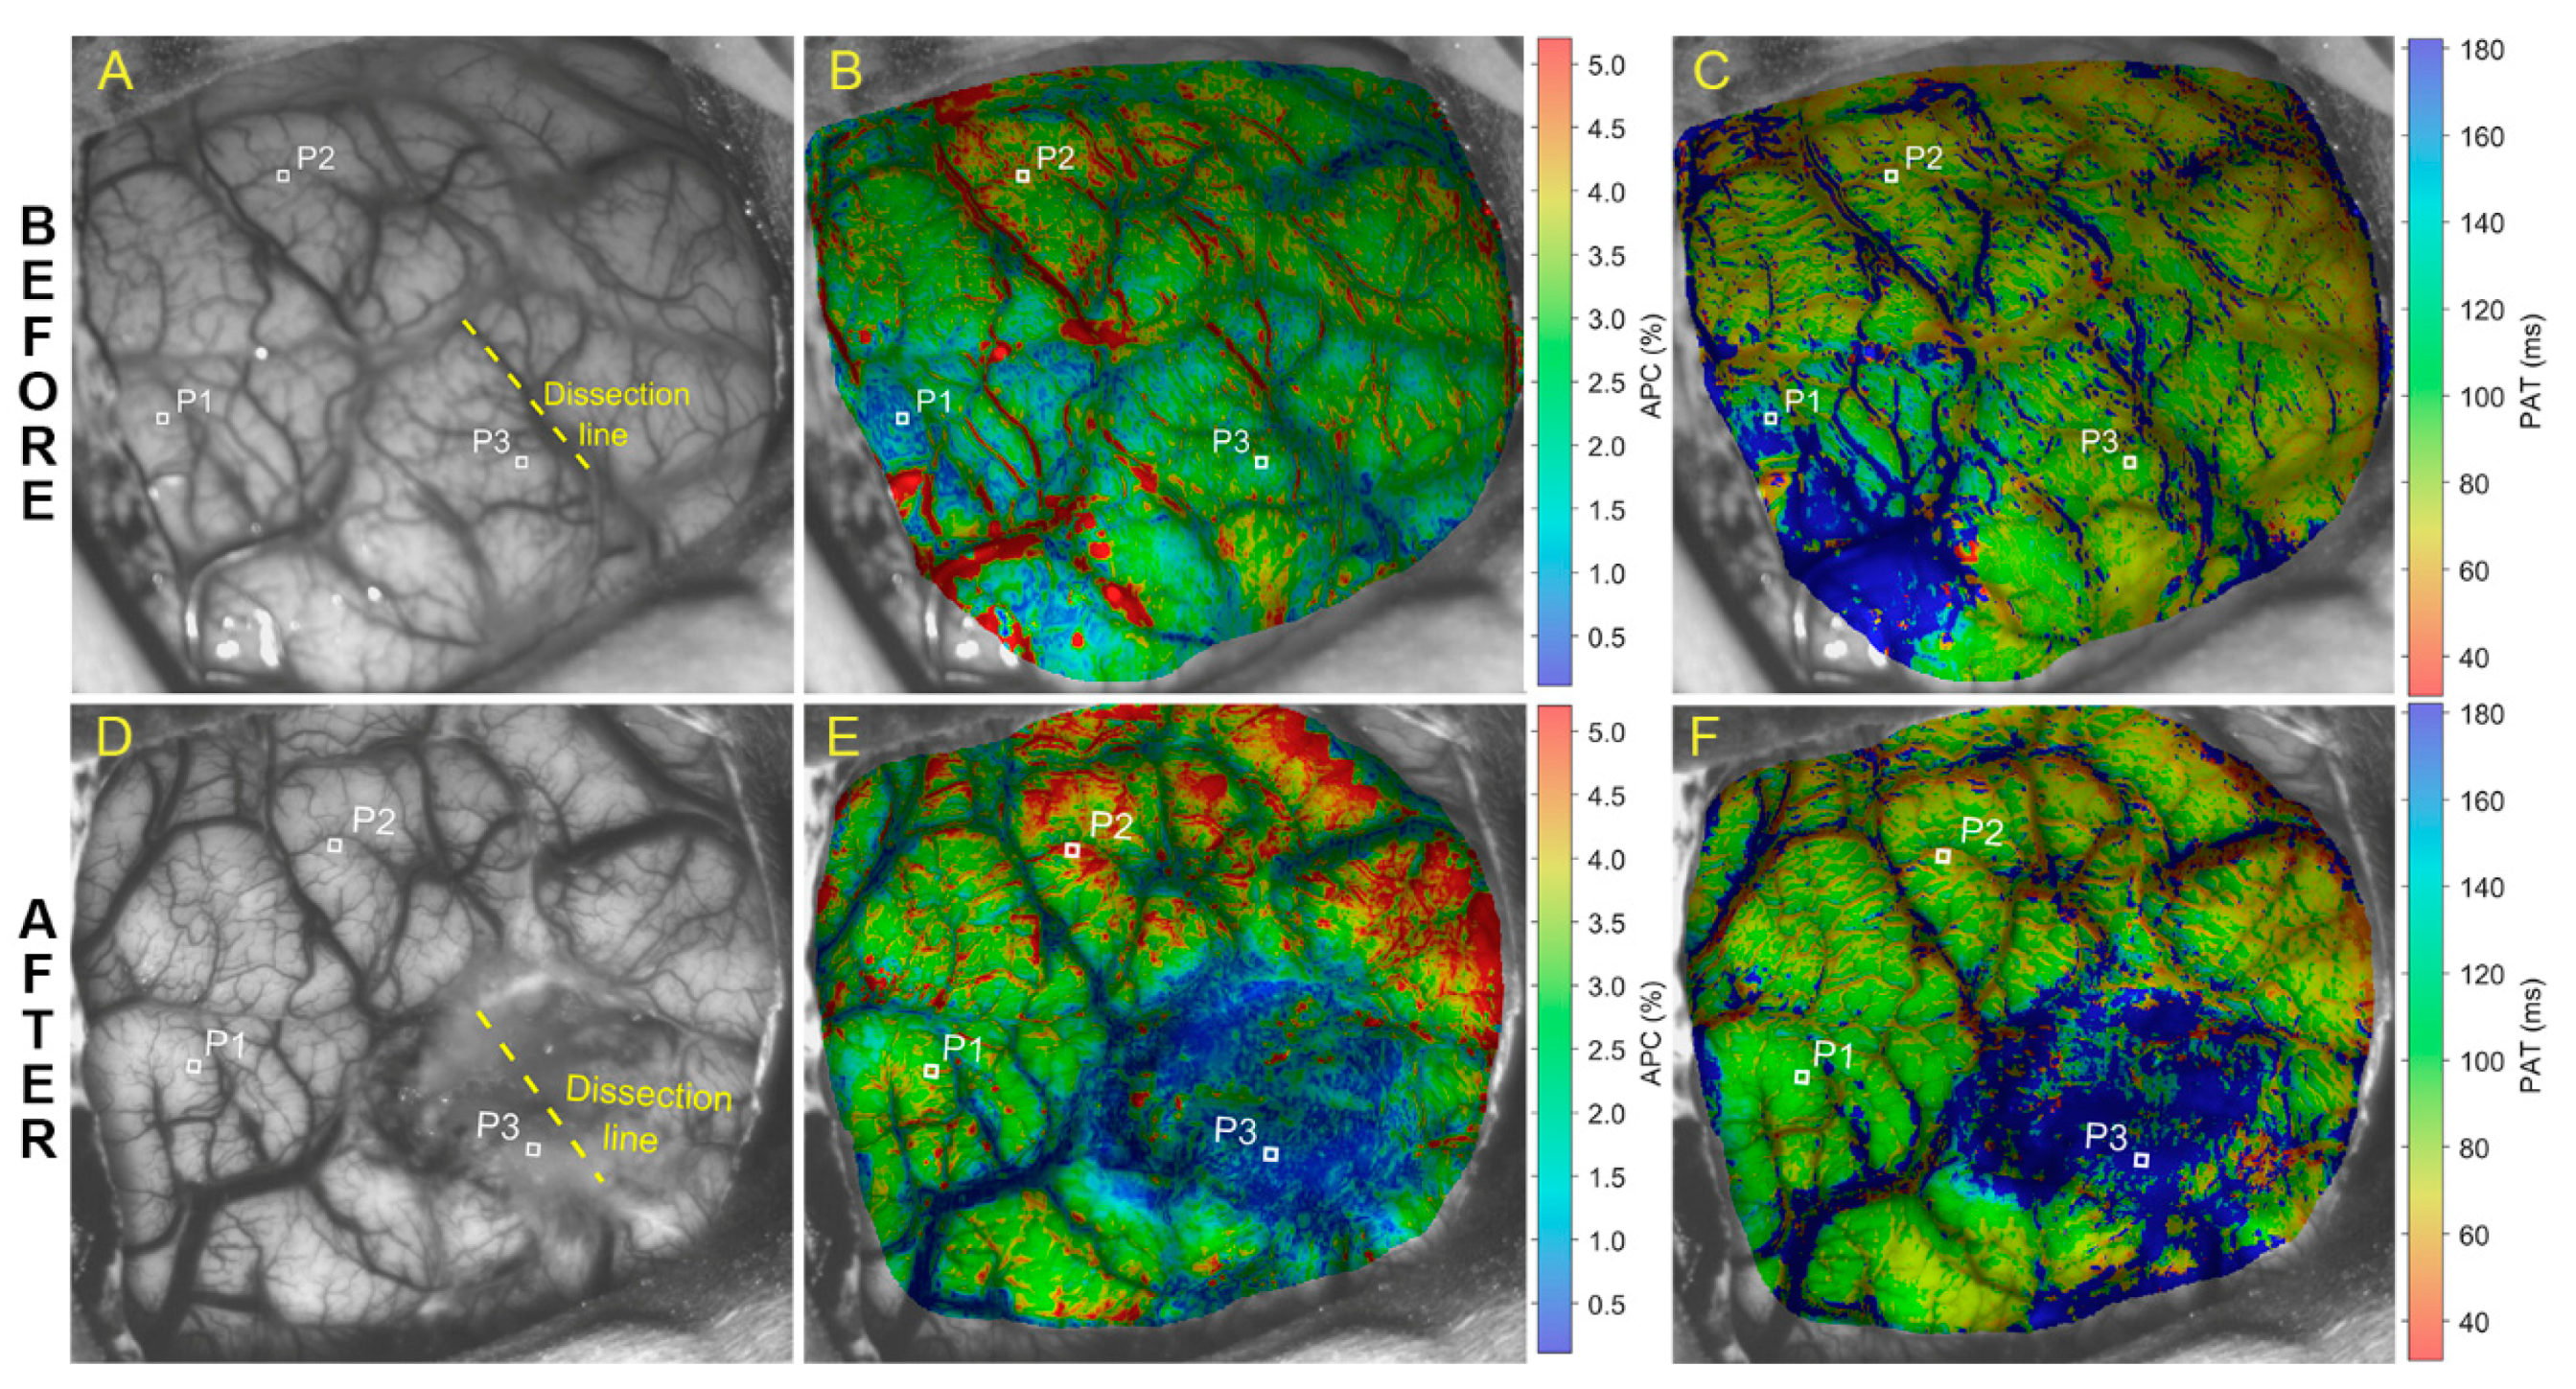

Parameters of cerebral blood-flow pulsations evaluated in the case of pathological formation of the brain right lateral ventricle are shown in Figure 1, where images of the upper and lower rows were obtained before and after surgery, respectively. Photographs of the open brain before and after tumor resection are shown in Figure 1A,D, respectively. The tumor was situated about three cm below the cortex in the brain right ventricle, near the region of the yellow dashed line (Figure 1A,D) marking the cortex dissection to access the tumor. Maps of APC (panels B and E) and PAT (panels C and F) in Figure 1 overlay respective images of the brain.

Before surgery, the amplitude of blood pulsations is distributed rather evenly over the cerebral cortex with the exception of the lower left part of the APC map with a reduced APC indicated in blue in Figure 1B. The mean APC in the lower left quarter of the map in Figure 1B is 1.12 ± 0.51% whereas it is 2.74 ± 0.68% in the rest of the APC map. Probably, these changes are explained by the mechanical effect of the volumetric process on the local hemodynamics of the cortex, leading to compression of the vessels by the tumor. Lack of uniformity in the spatial distribution of PAT (Figure 1C) was observed as well. The blue area in the same quarter of the PAT map means that the pulse wave reached this area with a greater delay than the rest of the cortex: 188 ± 65 ms vs. 82 ± 54 ms, respectively.

After tumor removal, a significant decrease in the amplitude of pulsations was observed in the area around the dissection of the pia matter (dark blue area in Figure 1E) that might be caused by drawing apart the pia matter to reach the tumor. While before surgery the APC average within this region was 2.14 ± 0.67%, it became 1.21 ± 1.02% after intervention. Notably, the mean PAT in the same area increased from 98 ± 70 ms (Figure 1C) to 237 ± 114 ms (Figure 1F). It is worth noting that significant increase in the average APC outside the dissection area was observed: 2.38 ± 1.01% before surgery vs. 3.48 ± 1.05% after it. The average PAT value outside the dissection region decreased moderately from 109 ± 61 to 81 ± 36 ms.

Figure 1. Mapping the blood pulsations parameters in the brain cortex in the case of a patient with a tumor: The upper and lower rows of images of the open brain were obtained before and after tumor resection, respectively. Panels (A) and (D) show photographs of the open brain with the dissection area indicated by a yellow line and three selected regions of interest (ROIs) marked as P1, P2, and P3. Spatial distributions of amplitude of the pulsatile component (APC) and pulse arrival time (PAT) overlaid with still images of the open brain cortex are shown in (B), (E) and (C), (F), respectively. The color scales on the right side of images (B) and (E) show APC in percent, whereas that of images (C) and (F) is PAT in milliseconds.